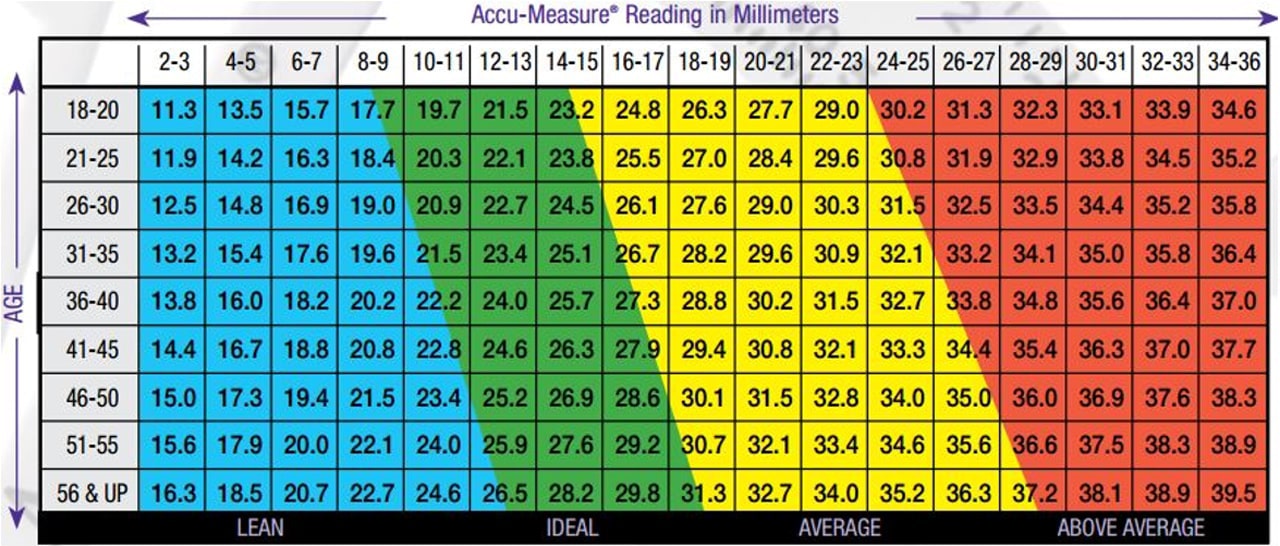

Hautfaltendicke (Calipometrie)

Bildquelle und weitere Infos zu dieser Methode finden sich hier:

Körperfettanteil berechnen: Wie viel Körperfett ist für Dich ideal? (marathonfitness.de)